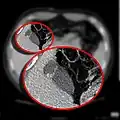

CT scan showing a phrygian cap

In medicine, a Phrygian cap is the folded portion of some gallbladders that resembles the Phrygian cap (a soft conical cap with the top pulled forward, associated in antiquity with the inhabitants of Phrygia, a region of central Anatolia). It is a normal anatomical variant seen in 1-6% of patients.[1] It is caused by a fold in the gallbladder where the gallbladder fundus joins the gallbladder body.[2] Apart from the chance of being mistaken for stones on a sonogram, it has no other medical implications nor does it predispose one to other diseases.[1]